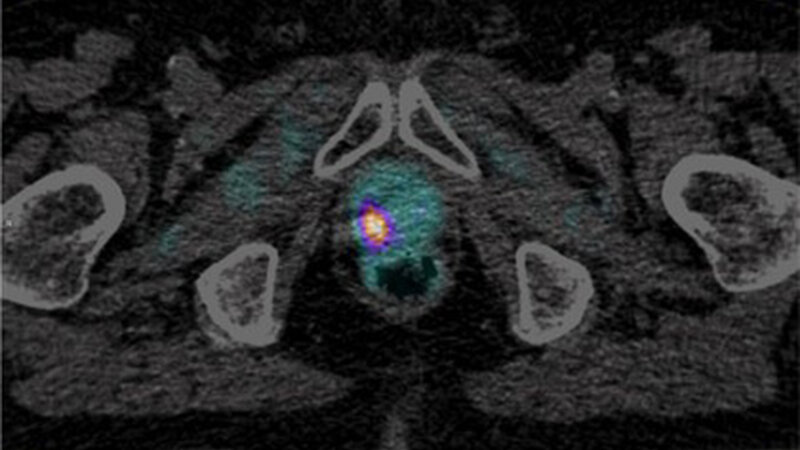

18F-Radiopharmaka nehmen in der Diagnostik und Therapie von Krebs- und anderen Erkrankungen einen immer bedeutenderen Stellenwert ein. Diese sind jedoch aufgrund der geltenden arzneimittelrechtlichen Zulassungen kommerziell nicht verfügbar. Um dem Patienten im niedergelassenen Bereich die Fortschritte auf diesem Gebiet dennoch zugute kommen zu lassen, scheint die einzige Lösung in der Einrichtung einer eigenen Radiochemie mit einem ambulanten Zyklotron zu bestehen. Mit ihrer Hilfe können für den Patientenbedarf entwickelte Tracer vor Ort produziert und ohne Zeit- und Qualitätsverlust unmittelbar z. B. für die PET/CT-Diagnostik verwendet werden. Führt man ferner die Untersuchung unter Maßgabe einer sich anschließenden Strahlentherapie durch, können die gewonnenen Daten direkt für die estrahlungsplanung genutzt werden und dem Patienten eine gesonderte CT ersparen.